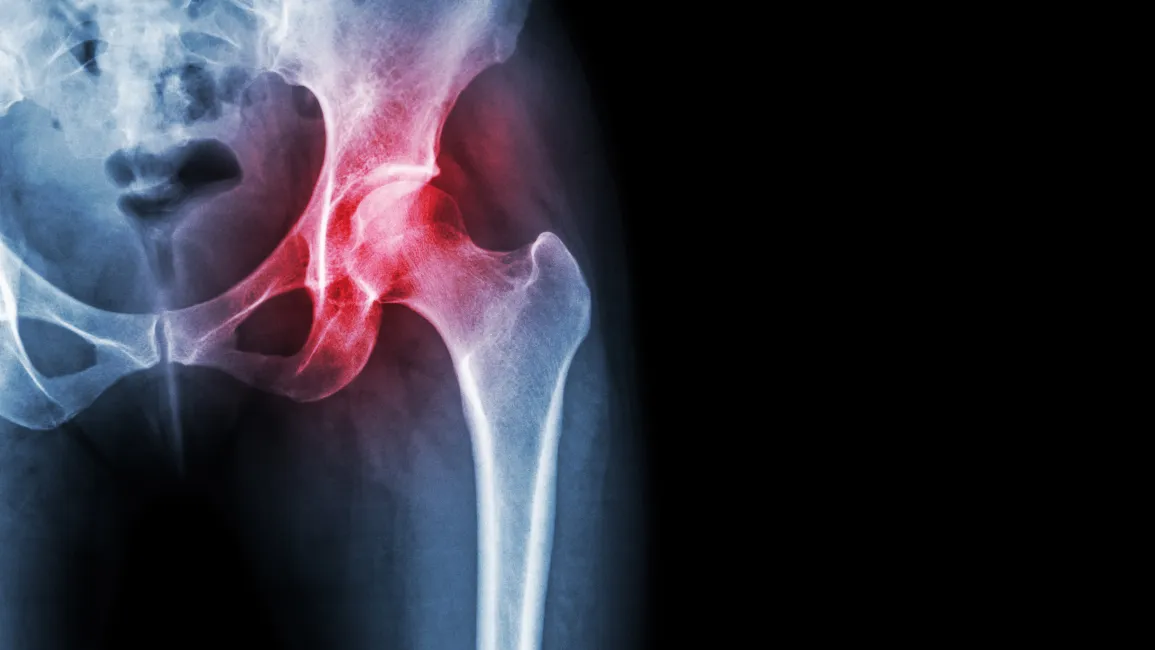

hip xray image

The progression of degeneration in the hip joint is the cause of most chronic hip pain. Although the symptoms may be very insidious at first, the process of degeneration typically takes many years to develop. If not addressed, this degeneration results in bone-on-bone deterioration and the eventual total joint replacement of the hip. In many cases, symptoms do not become severe until near the end stages. This typically means that many arthritis hip pain patients do not seek treatment or get x-rays until it is too late.

Symptoms of hip joint degeneration often vary depending on the severity of the case and where the damage to the joint has taken place. Some patients will experience pain with every activity they do, while others may only experience pain with extremely specific activities.